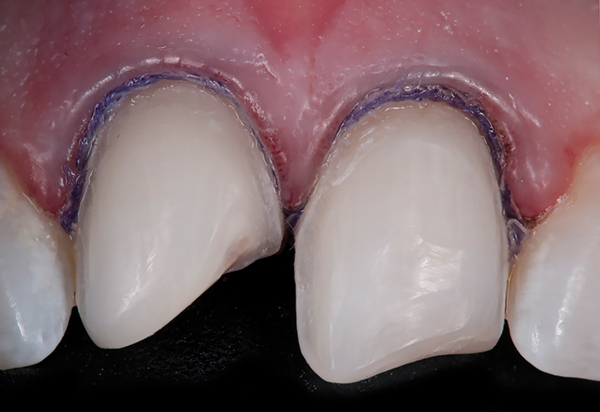

Fig 9. Preoperative view (Fig 9), preparation with composite block-out restoration (Fig 10), and final cementation of CL-IIb material (Fig 11) (final ceramic contour and stain by Steve Lee, CDT, MDC).

Fig 10. Preoperative view (Fig 9), preparation with composite block-out restoration (Fig 10), and final cementation of CL-IIb material (Fig 11) (final ceramic contour and stain by Steve Lee, CDT, MDC).

Figure 10

Fig 11. Preoperative view (Fig 9), preparation with composite block-out restoration (Fig 10), and final cementation of CL-IIb material (Fig 11) (final ceramic contour and stain by Steve Lee, CDT, MDC).

Figure 11